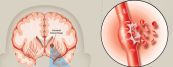

Nhồi máu não hay nhũn não xảy ra khi một mạch máu bị tắc, nghẽn, khu vực tưới bởi mạch đó bị thiếu máu và hoại tử. Nhồi máu não chiếm khoảng 80 - 85% trong tổng số các bệnh nhân tai biến mạch máu não. Để hiểu rõ hơn về bệnh lý nguy hiểm này, mời các bạn tham khảo bài viết dưới đây nhé!

Nhồi máu não chiếm từ 70-80% các trường hợp đột quỵ nhưng có thể chữa khỏi trong khi bệnh nhân bị xuất huyết não dễ tử vong hoặc tàn phế. Để hiểu rõ hơn về bệnh lý này, mời các bạn cùng tham khảo những thông tin dưới đây nhé!